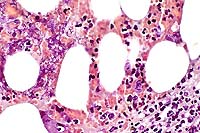

2x

obj

- Case 12-2. Lymph node. Extensive necrosis and inflammation

with focal areas of hemorrhage.

40x

- Case 12-2. Lymph node. Multifocally within zones suppuration

and necrosis, are multiple large colonies of bacteria.

obj, Brown & Brehn

- Case 12-2. Perinodal fat. Brown & Brehn staining

reveals that bacterial colonies are composed of short reddish-blue

(Gram negative) rods.

- AFIP Diagnosis: Lymph node: Lymphadenitis, necrotizing,

suppurative, diffuse, severe, with numerous bacilli, Siberian

polecat x black-footed ferret (Mustela eversmanni x M. nigripes),

mustelid.